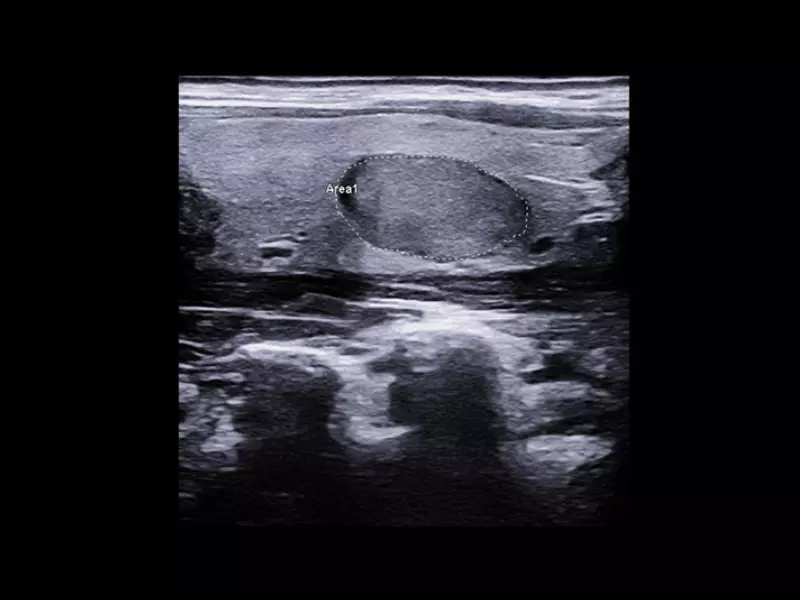

MyLab™9 Platform - High resolution imaging in testis

MyLab™9 Platform - High resolution imaging in testis

MyLab™9 Platform - XFlow in testis vascularization

MyLab™9 Platform - XFlow in testis vascularization

MyLab™X1 - Neck-lump

MyLab™X1 - Neck-lump

MyLab™X9 - Breast 01

MyLab™X9 - Breast 01

MyLab™X9 - Superficial 01

MyLab™X9 - Superficial 01